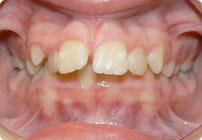

Femenino

Antes

Despues

Caso: 20 años

Adulto: Clase II,

Mordida Abierta Anterior

Sin extracción

4 series de alambres:

.016″, .022″, .0215″ x .028″, .019″ x .025″ Trenzado;

Elásticos en cajas

Triangulares TP Rosa, Verde, Azul

Retenedores: Inferior Fijo

Tiempo de tratamiento: 16 Visitas